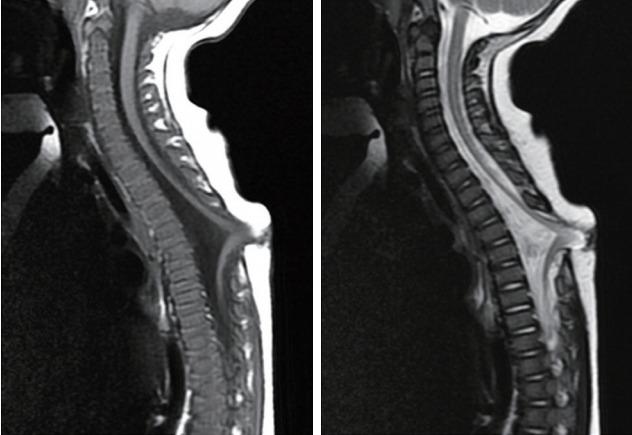

Spinal dysraphic lesions due to focal nondisjunction in primary neurulation are commonly encountered in paediatric neurosurgery, but the "fog-of-war" on these conditions was only gradually dispersed in the past 10 years by the works of the groups led by the senior author and Prof. Kyu-Chang Wang. It is now clear that limited dorsal myeloschisis and congenital spinal dermal sinus tract are conditions at the two ends of a spectrum; and mixed lesions of them with various configurations exist. This review article summarizes the current understanding of these conditions' embryogenetic mechanisms, pathological anatomy and clinical manifestations, and their management strategy and surgical techniques.

由于原发性神经管形成过程中的局灶性不分离导致的脊柱裂病变在小儿神经外科中很常见,但在过去10年中,由资深作者和王宇辰教授领导的团队的工作才逐渐驱散了这些病症上的“战争迷雾”。现在已经明确,有限性背侧脊髓裂和先天性脊柱皮样窦道是同一谱系两端的病症;并且存在各种形态的它们的混合病变。这篇综述文章总结了目前对这些病症的胚胎发生机制、病理解剖和临床表现,以及它们的治疗策略和手术技术的认识。